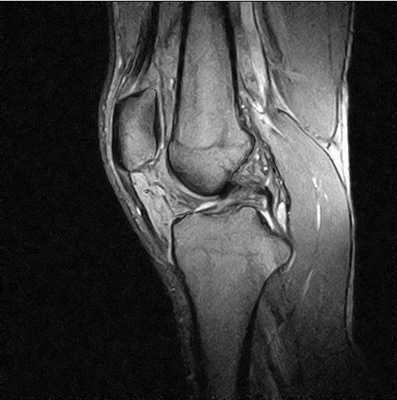

МРТ коленного сустава - фото (сагиттальная проекция)

МРТ лучше отображает связочный аппарат, мениски и прочие мягкие ткани колена.

Томография магнитно-резонансная показывает:

проблемы с хрящами (микроповреждения, трещины, отрывы, частичные разрывы);

состояние сухожилий и связок;

инфекционные процессы и воспаления;

поражение кровеносных сосудов, жировой ткани, мышц, окружающих сустав.

Явление ядерно-магнитного резонанса позволяет досконально изучить мягкие ткани. Кости на снимках видны недостаточно хорошо (по сравнению с КТ или рентгеном). Что дает МРТ коленного сустава? Исследование помогает выяснить сведения об окружающих сочленение структурах, по состоянию которых определяют скрытые (субхондральные) переломы: их нельзя или крайне трудно увидеть при рентгенографии. Полипроекционность, высокая разрешающая способность и возможность использования разных режимов сканирования — преимущества МРТ перед другими методами.

МР-сканирование позволяет визуализировать все составляющие коленного сустава:

- переднюю и заднюю крестообразные связки;

- сухожилие четырехглавой мышцы бедра;

- надколенник и его собственную связку;

- бедренную кость;

- жировое тело Гоффа;

- мыщелки (медиальный и латеральный);

- малоберцовую кость;

- медиальный и латеральный мениск;

- большеберцовую кость;

- боковые связки;

- ретинакулумы;

- суставную сумку;

- синовиальную жидкость.